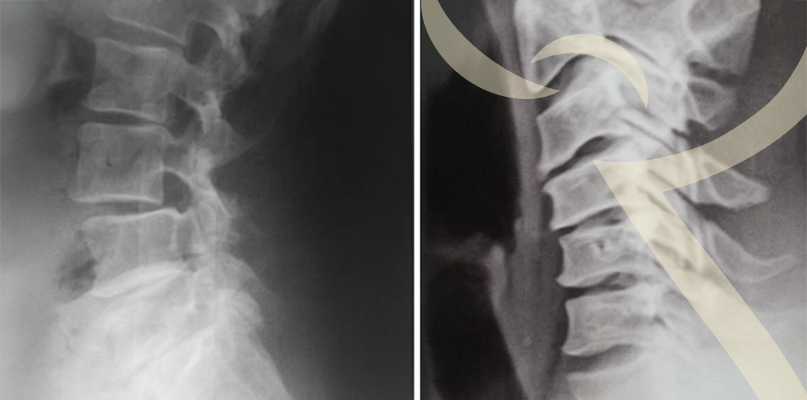

O bico de papagaio, ou osteofitose, é uma alteração na coluna vertebral causada pelo desgaste dos discos intervertebrais, geralmente associado ao envelhecimento. Esse desgaste leva à formação de osteófitos (pequenas pontas de osso nas vértebras) que, em alguns casos, comprimem nervos e geram sintomas.

- Dor localizada na região cervical ou lombar;

- Rigidez e limitação de movimentos;

- Formigamento ou dormência nos braços ou pernas, quando há compressão de nervos.